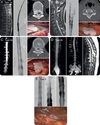

How well did you know this?

**RNM DE NEUROEIXO** - Encéfalo: sinais indireto de hipotensão liquorica - coluna: iinais de vazamento **MIELOGRAFIA DIGITAL COM SUBTRAÇÃO ou TOMOGRAFIA** - Possivel de identificar e topografar um vazamento de LCR (ex: diverticulo meningeo, ruptura meningea, Fistula LCR-Veia)

HIPOTENSÃO LIQUORICA A) Coleção de LCR reteoespinhal B) Vazamento periradicular C e D) Coleção epidural